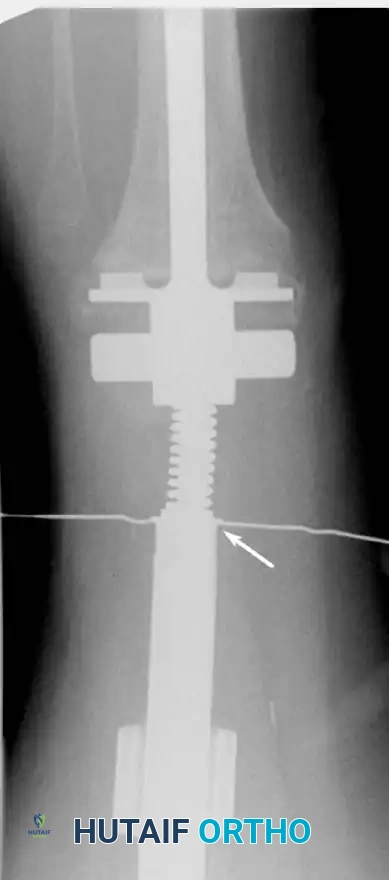

Advanced Reconstructive Modalities and Distal Extensions

While proximal humeral resections dominate shoulder oncology, tumors extending into the humeral diaphysis or distal humerus require equally complex limb salvage strategies. Total humeral replacement or distal humeral megaprostheses are viable options when the radial nerve can be preserved or grafted.

Intraoperative Imaging and Margin Assessment

Continuous intraoperative assessment using fluoroscopy and frozen section pathology is mandatory. The following images demonstrate various stages of complex upper extremity resections, allograft preparations, and prosthetic implantations across the humerus and elbow joint.

Distal Humerus and Elbow Reconstruction

When tumors involve the distal humerus, resection often requires sacrifice of the collateral ligaments and the articular surface of the elbow. Reconstruction is typically achieved using a linked, semi-constrained total elbow arthroplasty designed for oncologic defects.